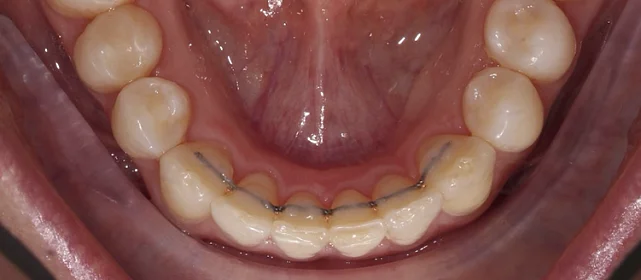

Прозрачные элайнеры Click на обе челюсти. Расширить зубные дуги, убрать скученность, выровнять линию смыкания. Основной набор — 32 капы. Срок — около 2 лет.

Зубы выровнены, скученность устранена, линия смыкания нормализована. Установлены несъёмные ретейнеры на обе челюсти, сняты слепки для ретенционных кап.

Решение: Поставили элайнеры Click на обе челюсти. Начали с 32 кап, но случай потребовал три дозаказа: 30, 10 и 10 кап — итого 82 капы за 30 месяцев. Количество дозаказов объясняется и сложностью случая (скученность плюс деформация кривой Шпее), и тем, что контрольные визиты были реже обычного из-за проживания за границей. Тем не менее результат достигнут: зубы ровные, смыкание в норме. На ретенцию пациентка приехала отдельно — зафиксировали ретейнеры на обе челюсти, сняли слепки для ретенционных кап.